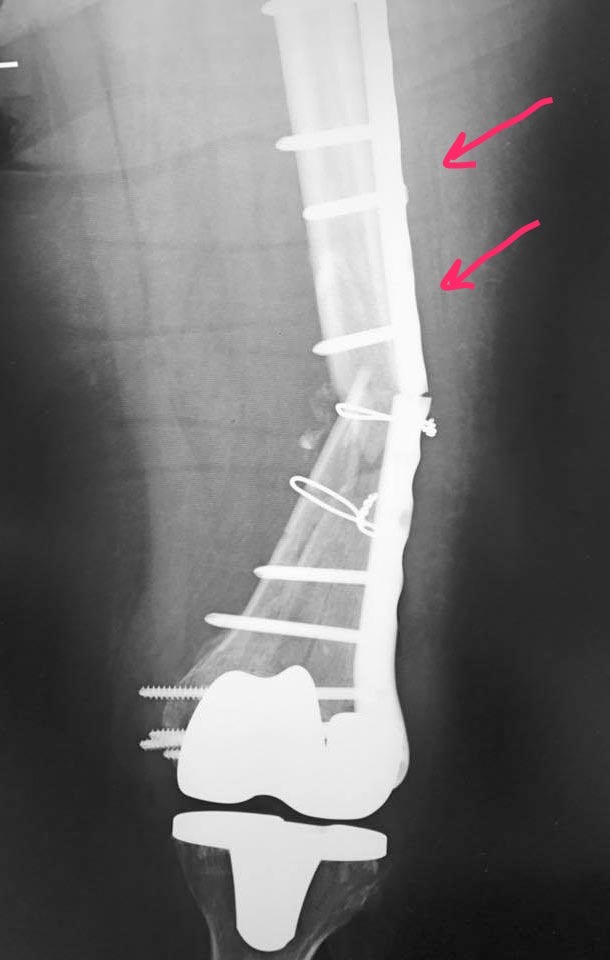

Re: Перипротезный перелом дистального отдела бедра

Реостеосинтез такой же пластиной. Костная пластика, убрать серкляж, и винты в отмеченных позициях тоже, то есть увеличить зону " работы" пластины. Или гвоздь.

Короткая рабочая зона. Это так, навскидку